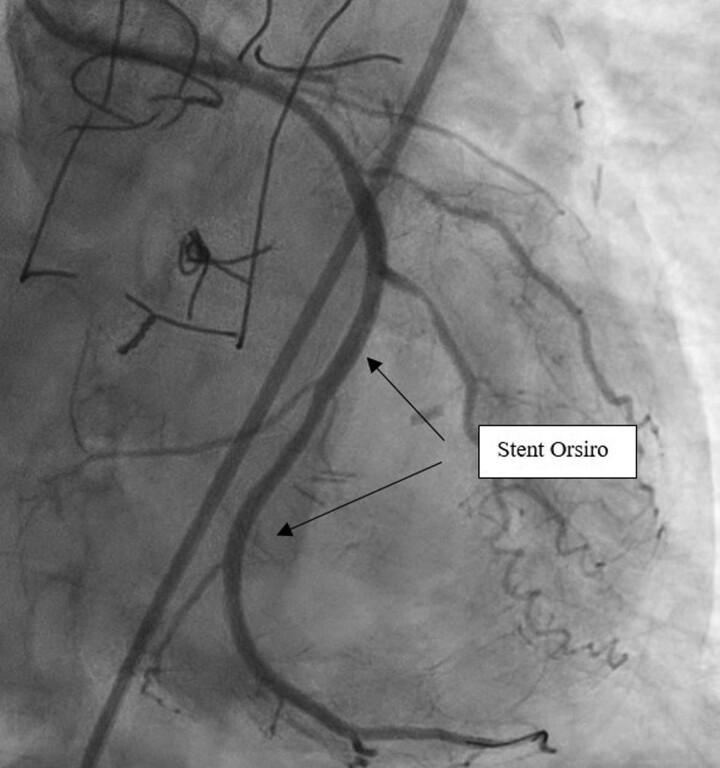

A 71-year-old man with history of LIMA to LAD coronary artery bypass surgery was admitted to the nephrology intensive care unit for acute kidney injury requiring dialysis. Due to rapid deterioration, altered left ventricular ejection fraction and elevated -troponin levels, an urgent coronary angiography was performed. It revealed a subtotal occlusion of the left subclavian artery prior to the origin of the LIMA to LAD graft. This was responsible for a severely altered coronary flow in the LIMA and LAD. Revascularization of the proximal left subclavian artery with a stent was performed, enabling instant recovery of distal coronary flows.

一名有LIMA至LAD冠状动脉旁路移植手术史的71岁男性因急性肾损伤需要透析而入住肾病重症监护病房。由于病情迅速恶化、左心室射血分数改变及肌钙蛋白水平升高,遂进行了紧急冠状动脉造影。结果显示在LIMA至LAD移植起点之前左锁骨下动脉几乎完全闭塞。这导致了LIMA和LAD中冠状动脉血流严重改变。对左锁骨下动脉近端进行了支架血管重建,使冠状动脉远端血流立即恢复。